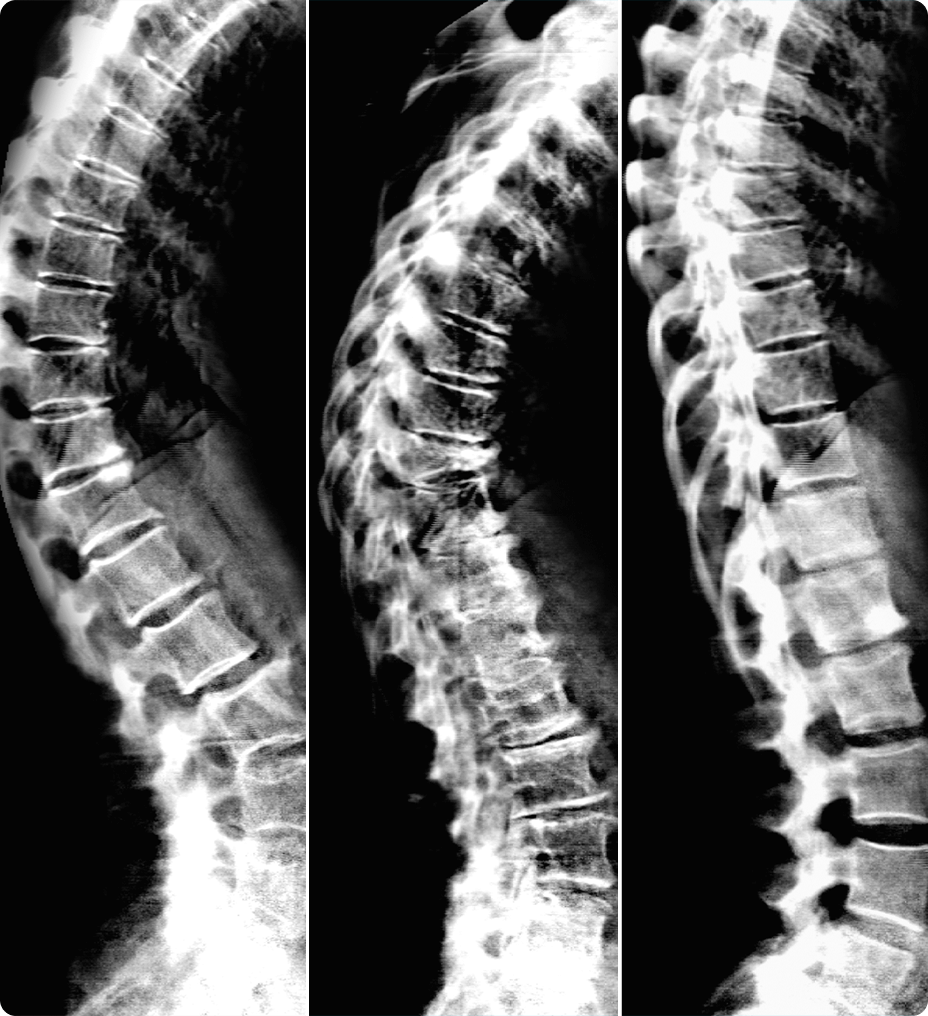

Améliorez votre qualité d’image IRM avec la technologie de reconstruction AIR™ Recon DL

Une meilleure imagerie, tout simplement